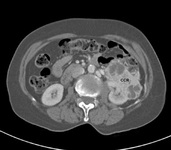

Tomografia computadorizada (TC) de carcinoma de células renais (CCR) do rim esquerdo

Do acervo pessoal do Dr Reese